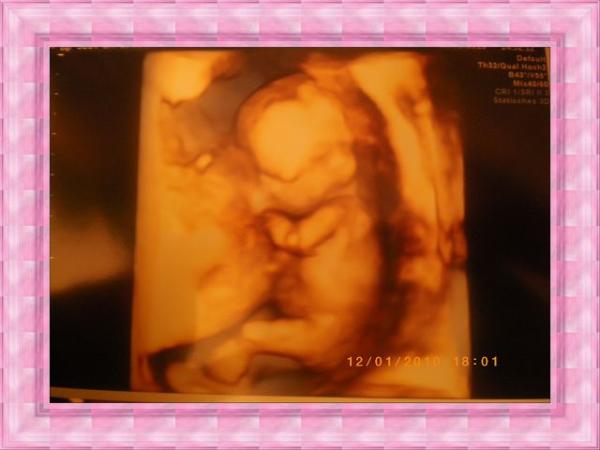

....der aufgrund meines Alters und der angeborenen Fehlbildungen von 2 meiner Kinder gemacht wurde. Und es ist alles ok!!! Mausi ist TOP fit hat geturnt wie ein Weltmeister und sogar den Schluckauf konnte man sehen wenn Sie immer gehopst ist. WAHNSINN. Schon faszinierend wie perfekt entwickelt sie sind obwohl sie ja noch sooooooooooooooooooo winzig sind. Hier mal ein Bild von heute , da der Scanner nicht funzt nur abfotografiert. LG eine Happy Zwergenmama74

Bild zu Heute früher Fehlbildungsultraschall - Forum für Juli - Mamis

Hallo Also Mausepups ist von Scheitel bis zum Po 6,8cm (entspricht 13+0) und ich war heute 13+2 war also 2 Tage kleiner aber wie gesagt die kleinen wachsen ja unregelmäßig und in Schüben. LG Zwergenmama74